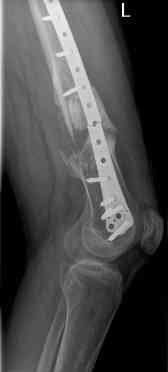

16 yr old boy, high energy motorcycle trauma trauma in July 2005 with:

- hip dislocation + acetabular fracture L

- distal femoral fracture L

- tibial shaft fracture L

- metatarsal fractures L

july 05: LISS femur, LCP plate tibia, double recon. plate post. acetabulum

oct 05: cancellous bone graft femur

aug 06: blade plate + bone graft

nov 06: revision blade plate

feb 07: retrograde nail + bone graft + BMP

may 07: dynamisation nail

sept 07: locking screw removal (max. dynamisation reached)

nov 07: persistant non-union distal femur; other fractures healed uneventfully.